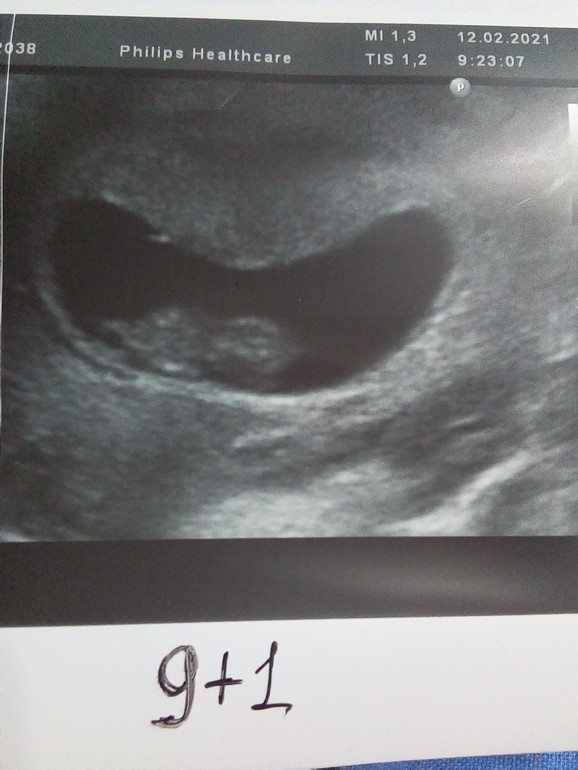

У нас получилось! Я беременна!По УЗИ поставили срок 9+4, по О 9+1:

ПЯ 38мм, КТР 26 мм, ЧСС 186 уд/ мин, ЖМ 5 мм, преимущественная локализация плаценты по передней стенке в дне матки.

Узистка с большим опытом сказала , что КТР мальчуковый, на этих сроках мальчики обычно опережают девочек. Дочку она мне угадала, посмотрим как в этот раз.

Как думаете , кто по методу Рамзи? ( фото сделано по животу) Пол поставила на удачу🤞